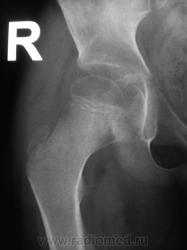

Пациент направлен на конрольное рентгенологическое исследование средней трети бедренной кости с целью оценки консолидации. Ранее - первичный снимок пациент был направлен на рентгенографию средней трети бедра, что и было сделано. Но, при производстве "контроля" рентгенолаборанты захватили тазобедренный сустав в прямой проекции, и возникли неясные сомнения по поводу головки, да и вообще...

Какой-то «змей 2х-головый» и впадина не слава богу. Надо или детских рентгенологов ждать или вторую проекцию делать.

Отлично все срослось. А что не нравится в головке? Остеопороз? Может быть после длительной иммобилизации.

Сама головка не нравится, особенно её нижне-медиальный отдел.

Согласна, что-то и меня в глазах головка бедра двоиться.

Пожалейте ребенка, не надо томографировать. Все укладывается в норму. Просто головка еще маленькая, а медиально - это шеечная шпора. Уж если не верите, снимите оба сустава одновременно.

Вероятно остеопороз головки от функционального щажения, разрушений не видно, капсула (мягкие ткани) параартикулярно - в норме...

Мне кажется, понятие "шеечная шпора" относится к тому возрастному периоду, когда головка бедра ещё толком не видна.

Согласен с теми коллегами которым, в нижнем квадранте вертлужной впадины видится фрагмент головки бедренной кости.В принципе тоже против "линейки", но "змея " добить надо.Почему бы не выполнить ультрасонографию сустава?

Интересная дискуссия. Жаль с опозданием увидел (однако же, много времени уходит, пока всё на сайте просмотришь). На мой взгляд, патологии головки нет, без фрагментации, проекционно пересекается с тенью обызвествляемого Y-хряща. Под головкой медиально, несомненно, есть остеопороз, придающий нечеткость картине. Впрочем, регионарный остеопороз имеет место вследствие закономерной атрофии после иммобилизации. Сюда же наслаивается субстрат т.н. фигуры серпа, еще не оформленный. Впадина нормальная. Кость срослась - замечательно, всем бы такие результаты. Реабилитация обязательна.